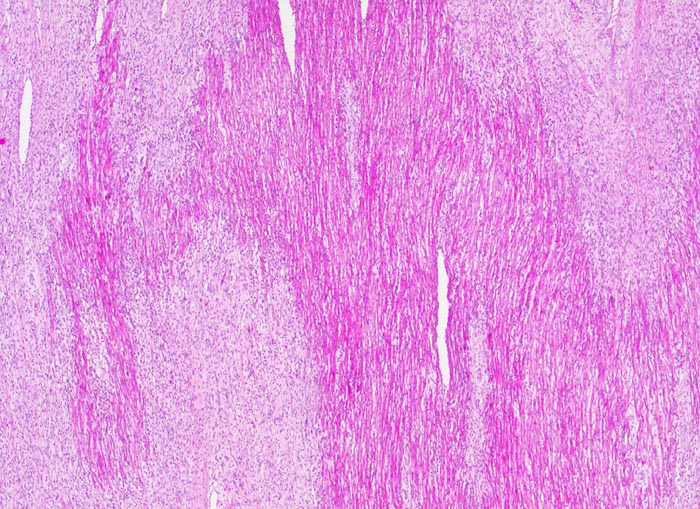

Subakute histiozytäre nekrotisierende Virusmyokarditis

Entzündung infektiös

Herz links

Grobfleckige subakute Nekrosen (helle Areale).

Lymphohistiozytäre interstitielle Pneumonie.

Myokarditis mit kardiogenem Schock.

Trotz negativem Virusnachweis ist der Befund gut vereinbar mit einer viralen Myokarditis.

Histologie

25